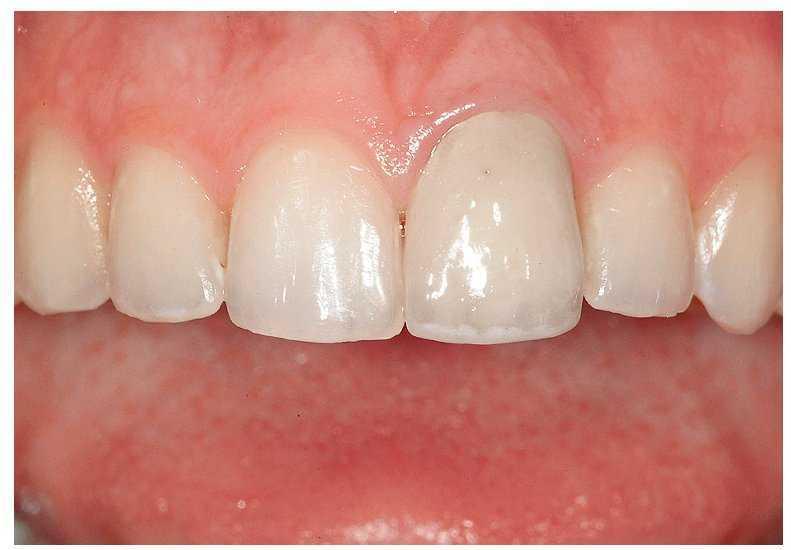

Una mujer de 21 años se mostraba insatisfecha con el entorno periodontal y el color de su corona en el diente 21, que le había sido colocada apenas un año antes tras un accidente. La anamnesis arrojó resultados normales. Durante el examen clínico, el color de la corona se reveló insatisfactorio. La encía estaba irritada y presentaba una recesión; el margen discurría 2 mm más hacia apical que en el diente 11 adyacente (fig. 3a). La corona estaba ligeramente sobrecontorneada en el margen. No pudo esclarecerse si la recesión gingival -el principal problema desde el punto de vista clínico- era atribuible al ajuste deficiente de la corona, al trauma original o a una combinación de ambos.

Fig. 3a. Vista desde frontal. La corona había sido colocada menos de un año antes del tratamiento aquí descrito.